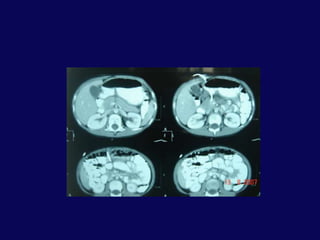

SK 6,E20 Gün önce bisikletten düşme dış merkezde taip batın distansiyonu gelişmesi üzerine İTF ne sevkFM: Distansiyon ve yaygın hassasiyet

BT: pankreas orta hatta laserasyon ve peripankreatik sıvı

Peripankreatik sıvıya perkütan drenaj kateteri . İlk gün 750 cc drenajİşlem sonrası 2. gün genel durum iyi.  Dren debisi 200 ccDren debisi giderek azalan hastanın 4. günde debisi 100 cc. Dren kültürü steril.7. gün kontrole gelmek üzere taburcu

Hasta işlem sonrası 23. gününde ateş, bulantı, kusma şikayetleriyle yeniden yatırıldı.BT’ de karaciğer ve mide arasında 6x5 cm’lik bir koleksiyon tespit edildi. Perkütan drenaj uygulandı. 200 cc geleni oldu.

Hastanın ilk konan dreninden geleni olmaması üzerine çekildi. Yeni drenden 150 cc geldi. Hasta işlem sonrası 3. gününde kontrole gelmek üzere taburcu edildi. 3. hafta kontrolde debi olmaması üzerine dren çekildi